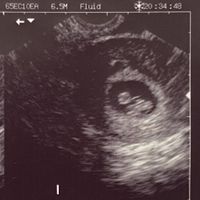

Hola! Quería preguntaros si entendéis el método Ramzi si sabéis que puede ser. Os lo agradecería muchísimo. Es una ecografía de 7 semanas